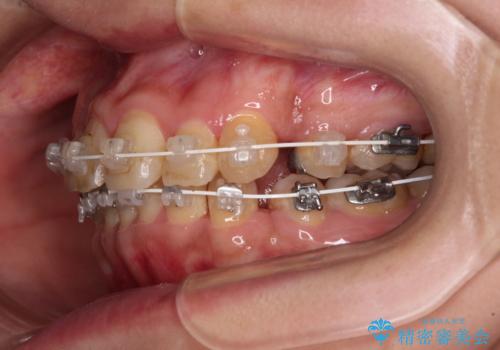

当院では、張り替える必要のある部位は張り替えることで継続することとし、抜歯スペースを閉じていくように治療を行うこととしました。

後戻りにリカバリーに少し時間を要しましたが、1年強の期間で無事に治療を終えることができました。